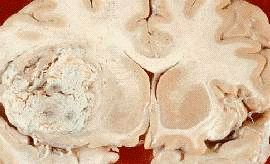

мозку, вздовж стінок шлуночків мозку та проростають у кору (рис. 11) [42].

Рис.11. Олігодендрогліома,

локалізована у лобній долі мозку (позначена стрілкою)

спеціалізованими клітинами мозку (рис. 12).